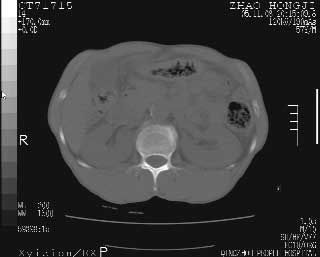

临床资料:男性,57岁,上腹部疼痛并5天,突然加重并延及全腹伴恶心5小时入院。胰淀粉酶化验在正常范围。检查:腹肌紧张,全腹压痛、反跳痛,尤以右上腹部为著。肠鸣音减低。血常规:wbc14.6x10/9, n:11.3x10/9 ,血压:135/90mmhg. 胸部透视:腹部肠腔轻度张气,未见其它异常改变。

肝缘见少许气体,胰尾部见少许气体包饶(蓝色圈),12指肠上部或球部邻近胆囊周边也可见少许气体影(黄色圈),并忖托出胆囊壁,12指肠远段肠道内未见明显气体(白色箭)。

肝脏前缘见少量积气、胰尾部见少许气体包饶,肾前筋膜未见增厚,临床淀粉酶不高,意见:上消化道穿孔。

入院3小时后行剖腹探查术,见腹腔内大量脓性混浊液约1000ml,十二指肠球部溃疡穿孔,溃疡面约2.5x2cm,穿孔直径约0.6cm。胃内容物外益,周围组织炎性水肿明显。行十二指肠穿孔修补术。术后诊断:

1、十二指肠溃疡穿孔

2、弥漫性腹膜炎

对于少量的腹腔游离气体,ct检查较普通透视有绝对的优势,它不仅可以看到肝脏前上缘的气体,而且还能够看到小网膜区的游离气体。从而可以肯定诊断。各位分析战友的很好,感谢大家的参入!